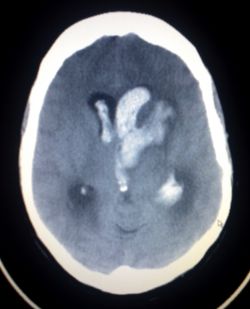

דימות נוירו-וסקולרי חד של דמם מוחי

רקע: הדמיה מוחית היא הכרחית לביסוס אבחנת דמם תוך מוחי ושבץ איסכמי. הרגישות של בדיקת MRI ו-CT לאבחנת דמם תוך-מוחי היא דומה וקרובה ל-100%. בדיקת MRI היא בעלת עדיפות מזערית בזיהוי דמם תוך-חדרי קטן (100% מול 97%), עדיפה לזיהוי דמם בשלבים הכרוניים, כמו כן עדיפה למציאת מיקרו-דימומים וסידרוזיס שטחי (ראו בהמשך).

הדמיית מוח בשלב החד היא בעלת יכולת לספק מידע פרוגנוסטי ולסייע במעקב אחר ההתפתחות של הדימום בדגש על התפשטות הדמם, שהיא גורם מנבא הידרדרות נוירולוגית, תמותה ופרוגנוזה גרועה. בין 26% ל-38% מהמטופלים יסבלו מהתפשטות הדמם. במרבית המקרים התפשטות הדמם מתרחשת בשעות הראשונות, אולם בכ-6% מהמקרים ההתפשטות מתרחשת 12–24 לאחר היארעות הדמם, עם שיעור אפסי בלבד לאחר 24 שעות. הופעה של דמם תוך-חדרי חדש בהדמיית ביקורת קשורה גם כן בפרוגנוזה גרועה, אינה נדירה (21%), ולרוב מתרחשת במהלך היממה הראשונה.

זיהוי spot-sign בבדיקת CTA או זיהוי של מדדים אחרים בבדיקת CT ללא חומר ניגוד (כגון אזורים בעלי צפיפות שונה בתוך הדמם, פלס נוזל, גבולות לא סדירים) יכולים לסייע לזהות את המטופלים אשר נמצאים בסיכון להתפשטות של הדמם. Spot sign נמצא כמדד מנבא לפרוגנוזה גרועה והחמרה נוירולוגית, אם כי הערכים המנבאים, החיובי והשלילי, של spot sign להתפשטות הדמם אינם גבוהים. משתנים נוספים שנמצאו כקשורים להתפשטות הדמם כוללים נפח דמם ראשוני נרחב, זמן קצר ממועד הופעת התסמינים ועד ביצוע ההדמיה, ושימוש בנוגדי קרישה. קיימים מספר סולמות המשלבים מדדי הדמיה ומשתנים קליניים במטרה לחזות את הסיכון להתפשטותו של הדמם, אולם אלו טרם נבדקו במחקרים פרוספקטיביים גדולים.

ביצוע בדיקת CT חוזרת משמשת להערכה ולשלילת התפשטות של הדמם, הידרוצפלוס או בצקת. במטופלים עם מצב הכרה שמור ובדיקה נוירולוגית יציבה, ביצוע בדיקת CT 6-24 שעות לאחר הופעת הדמם היא מספקת במרבית המקרים לשלילת התפשטות של הדמם ולקביעת הנפח הסופי של הדימום. ביצוע בדיקות הדמיה נוספות לאחר 24 שעות נועד לאבחן סיבוכים מוקדמים של דמם תוך-מוחי. ביצוע הדמיות חוזרות לאחר 24 שעות מומלץ בעיקר בהתאם למצבו הקליני של המטופל. יש לשקול ביצוע הדמיות נוספות בקרב מטופלים עם הידרדרות נוירולוגית או במצב הכרה ירוד אשר מגביל את יכולות הבדיקה הקלינית. ביצוע הדמיות חוזרות גם בקרב מטופלים יציבים קלינית מקובל, אך מרבית המחקרים העריכו צורך זה במטופלים עם דמם טראומטי ולא עצמוני, ולכן היעילות של ביצוע הדמיות אלו אינה ידועה.